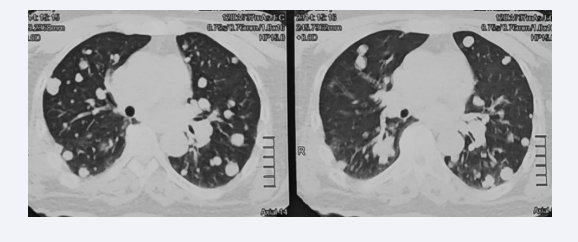

On the thoracic level (Figure 4), there was a right apico-dorsal tissue process with costal lysis opposite, parietal and vertebral invasion associated with multiple nodules scattered over both lung fields, giving a cannon ball appearance, and pre vascular mediastinal, Barety’s lodge, aorto-pulmonary window and left hilar enlarged lymph nodes.

Thoracic level of cervicothoracic CT scan showing a right apico-dorsal tissue process with costal lysis, parietal and vertebral invasion  associated with a cannon ball appearance and mediastinal adenopathies

Figure 4: Thoracic level of cervicothoracic CT scan showing a right apico-dorsal tissue process with costal lysis, parietal and vertebral invasion associated with a cannon ball appearance and mediastinal adenopathies